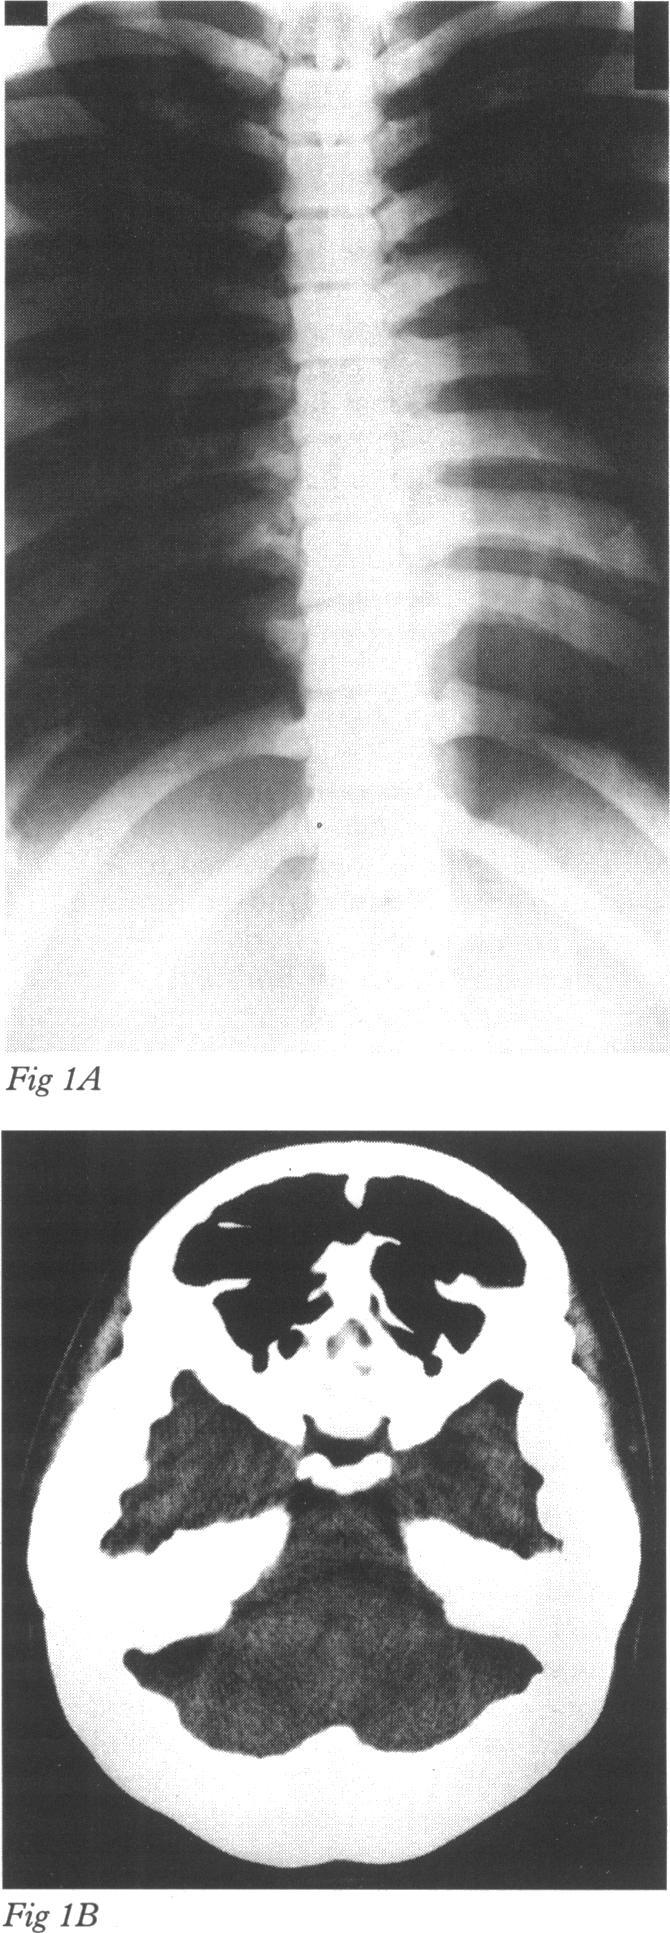

Candida endophthalmitis.

Br J Ophthalmol. 1995 Dec;79(12):1141-2. doi: 10.1136/bjo.79.12.1141.

原文链接:https://pmc.ncbi.nlm.nih.gov/articles/PMC505360/